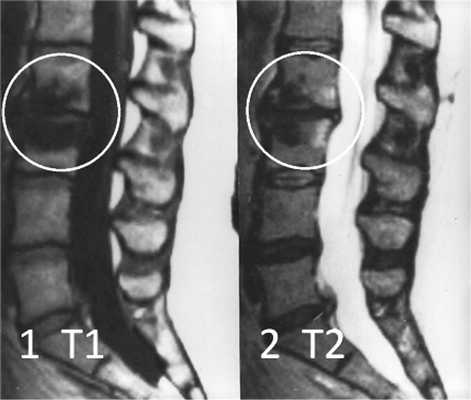

Изменения сигнала по типу MCh3 встречаются наименее часто и характеризуются гипоинтенсивным сигналом на T1- и Т2-ВИ на МРТ (рис. 3) [10]. Гистологически этот тип не изучался. На микро-КТ выявляются изменения, связанные с повышением уровня образования костной ткани и снижением ее резорбции [11]. На изображениях, полученных при проведении рентгенографии и мультиспиральной компьютерной томографии (МСКТ), этот тип характеризуется значительным уплотнением костной ткани — остеосклерозом [19, 20].

Рис. 3. Изменения на МРТ по типу MCh3. 1 — гипоинтенсивный сигнал на T1-ВИ; 2 — гипоинтенсивный сигнал на Т2-ВИ.